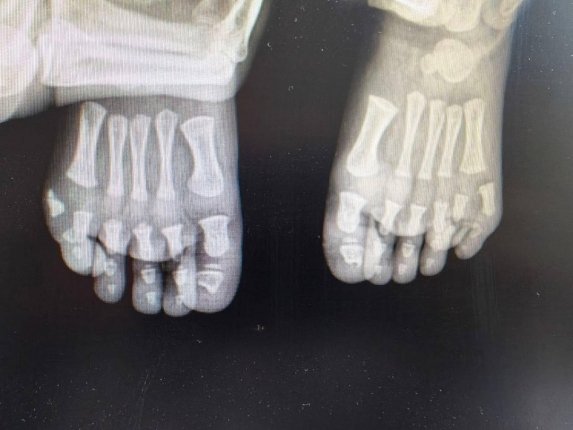

Лишние пальцы мешали ходить мальчику из Подмосковья

Рентгенография

В Подмосковье хирурги прооперировали мальчика с лишними пальцами на обеих стопах. Одна операция уже проведена, впереди — второй этап лечения. Об этом сообщили в Минздраве области.

Родители обратились к врачам из-за необычной особенности ребенка — на каждой ноге у него было больше пальцев, чем положено. После обследования специалисты поставили диагноз — врожденная аномалия развития, при которой формируются лишние пальцы. Такое состояние нередко связано с наследственными факторами.

Совместно с семьей было решено провести лечение поэтапно. Сначала врачи выполнили операцию на одной стопе — лишний палец удалили, а структуру восстановили. По словам медиков, вмешательство позволило не только исправить физическую проблему, но и предотвратить возможные психологические трудности в будущем.

После восстановления планируется аналогичная операция на второй ноге. Врачи рассчитывают, что после курса реабилитации ребенок сможет вести обычный активный образ жизни без ограничений.